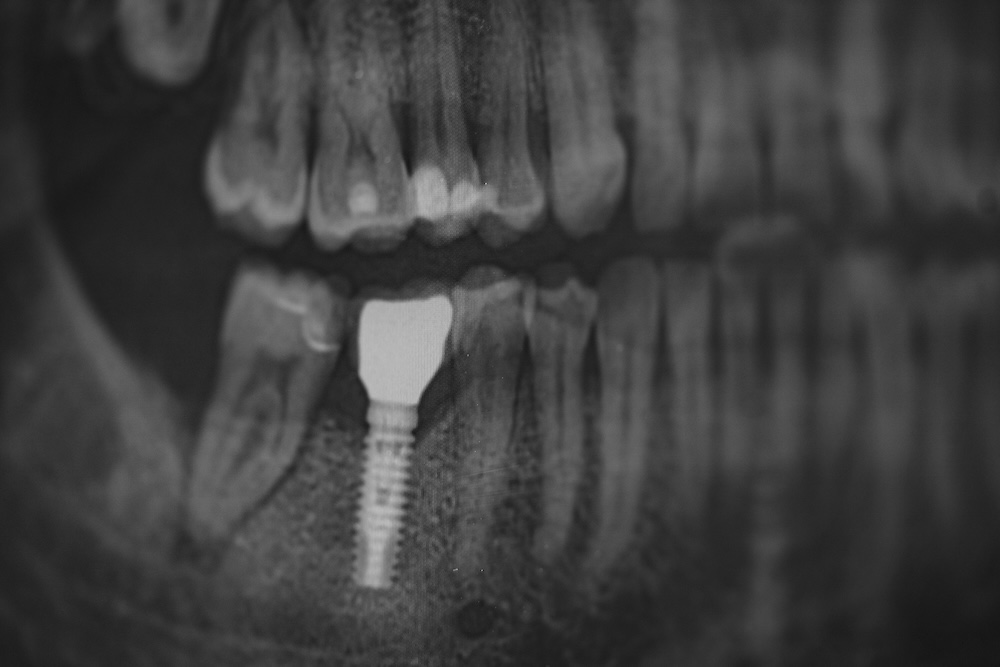

Ein Implantat ist eine künstliche Zahnwurzel aus Titan, die fest im Kiefer verankert und von unserem Körper wie körpereigenes Gewebe angenommen wird. Die künstliche Zahnwurzel wächst im Kiefer fest an und so kann Zahnersatz wie eine Krone, Brücke oder Prothese mit gutem Halt darauf befestigt werden. Eine optimale Option für einen festsitzenden Zahnersatz nach Zahnverlust.